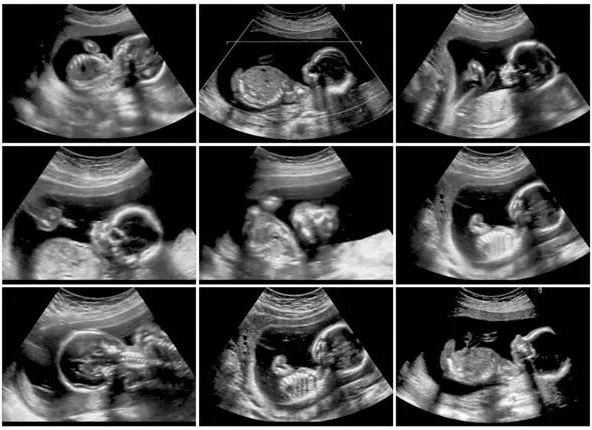

First Trimester Screening

Performed during 11 to 13 weeks of pregnancy

Includes blood tests and ultrasound scan (NT scan)

Helps assess the risk of chromosomal conditions such as Down syndrome

Evaluates certain pregnancy-related markers in maternal blood

Provides early information about fetal health

Second Trimester Screening

Usually performed during 15 to 20 weeks of pregnancy

Includes blood tests often known as triple or quadruple marker screening

Helps assess the risk of chromosomal abnormalities and neural tube defects

Provides additional information about fetal development